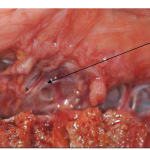

Photo INSERTIONS DE LA DURE-MERE SUR LE RACHIS Une anatomie redécouverte 9